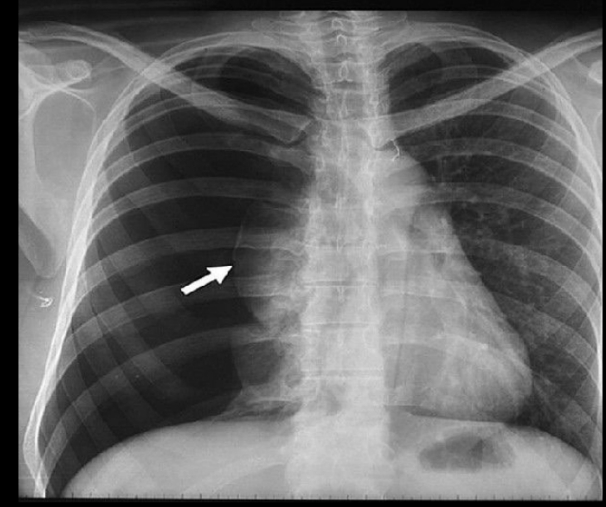

Qué se ve en una Rx de un hemotórax

• Derrame pleural

• Borammiento de la silueta cardíaca